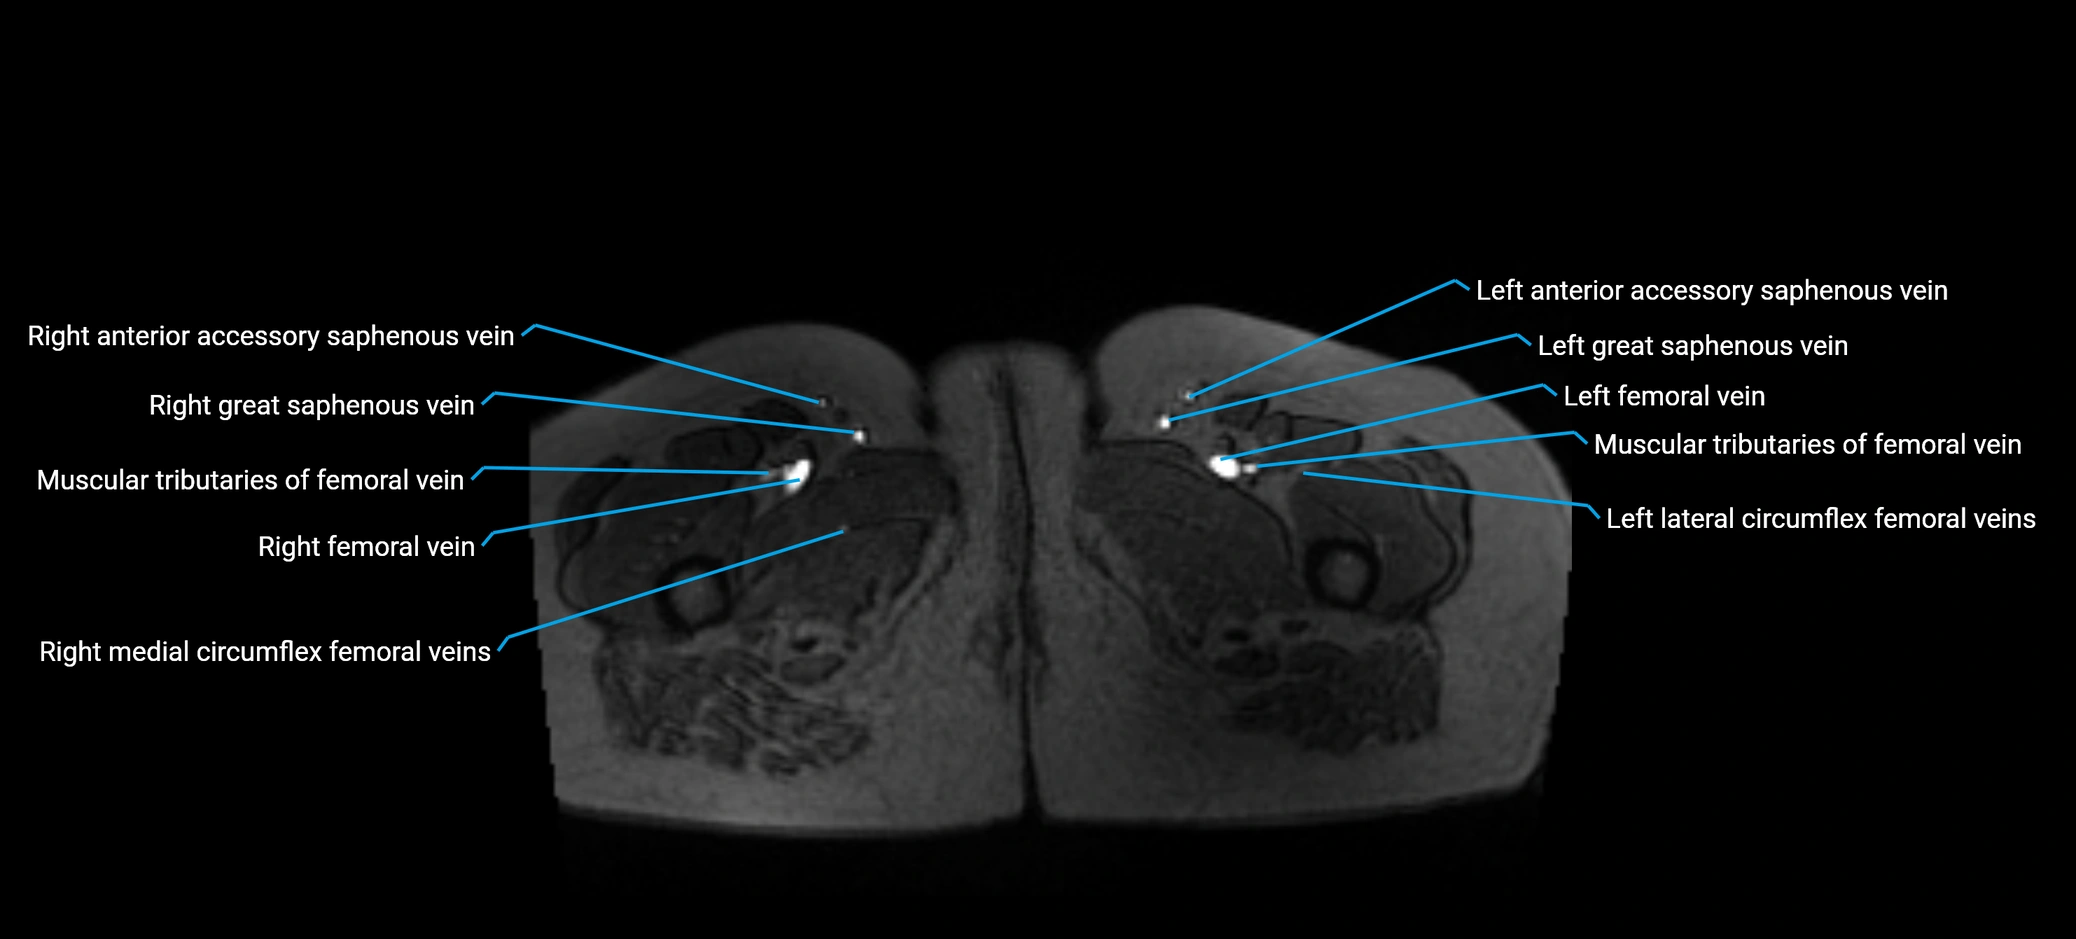

MRI image

image